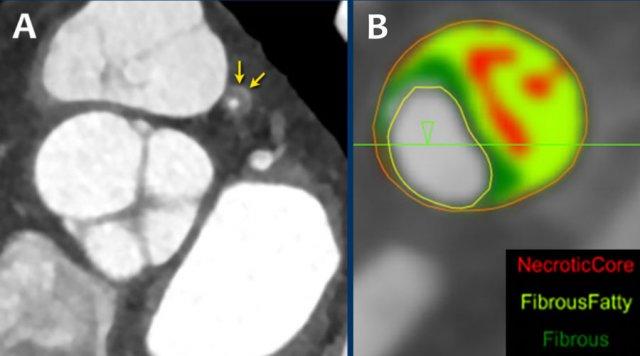

A: On the coronal image the so-called napkin-ring sign (dark area adjacent to the lumen, surrounded by a higher “ring-like” attenuation (white arrows). B: Tissue characterization on CT by HU number

Napkin-ring sign

The Napkin-ring sign is a qualitative high-risk plaque feature

on CTA (13).

It is defined as a central low-attenuation area adjacent to the coronary lumen

and a higher “ring-like” attenuation tissue surrounding this central area (14).

On histology, the area of low-attenuation corresponds to the necrotic core,

while the “ring-like” outer area correlates with fibrous plaque tissue.

The Napkin-ring sign is strongly associated with major adverse

cardiovascular events (15).